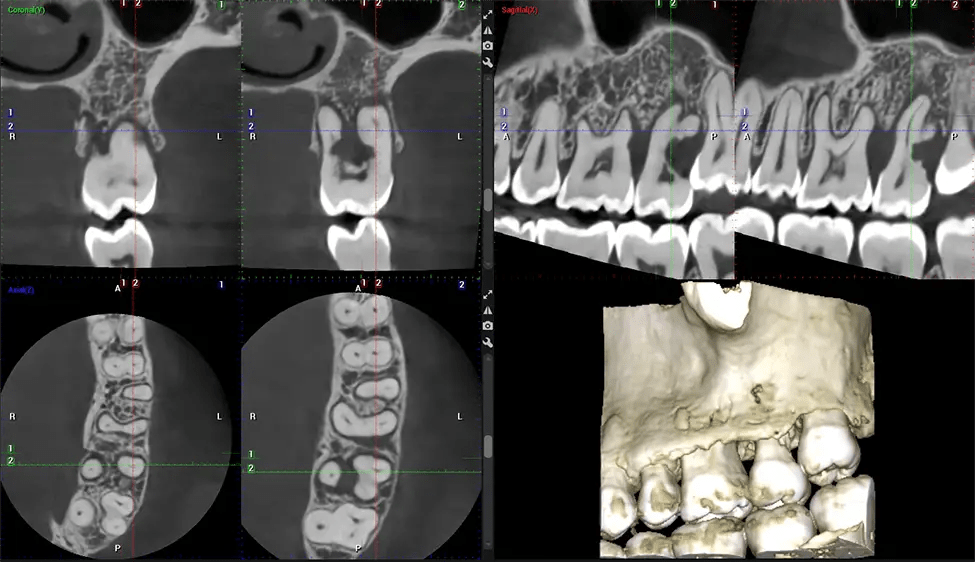

Cone Beam Computed Tomography (CBCT) is an advanced imaging technique used in dentistry and maxillofacial surgery to obtain detailed 3D images of the oral and maxillofacial structures. At Dr G Dental Studio, our CBCT scanners utilize a cone-shaped X-ray beam and a specialized detector to capture images from different angles. A computer then combines these images to create a 3D representation of the patient’s oral anatomy.

This 3D scan, called cone beam computed tomography, gives your dentist a more complete image of your oral anatomy and disease processes than a traditional X-ray. Unlike conventional X-rays, which capture a 2D image of your mouth from various angles, a 3D scan takes multiple digital X-rays for one image. It provides a complete view of your jaw, teeth, nerves, and soft tissues. This enhanced view allows dentists to detect minor issues not visible in traditional 2D scans, such as impacted wisdom teeth or bone fractures in the sinus cavity.

After the scanning process, the captured X-ray images are processed by the CBCT software, which applies algorithms to reconstruct a detailed 3D image of the scanned area. The software compiles these individual X-ray images and creates a digital 3D representation of the patient’s anatomy. The reconstructed 3D CBCT image can be viewed and analyzed by the dentist or radiologist. This image can be manipulated, rotated, and zoomed in or out to examine specific structures and evaluate the patient’s condition.